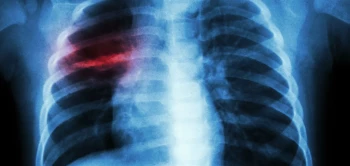

Preventieve vaccinatie is één van de meest doeltreffende en kostenbesparende strategieën in de gezondheidszorg. Voor de bestrijding van tuberculose (tbc) hebben we dit jaar op de kop af, al een eeuw het zogeheten BCG-vaccin tot onze beschikking. Het bespaart daarmee veel ellende en vooral kinderlevens. Maar deze 'jubilaris' faalt helaas bij het terugdringen van ernstige longtuberculose in (jong-)volwassenen, waardoor tbc alleen het huidige covid boven zich vindt in de lijst van meest bedreigende infectieziekten ter wereld.

In eerder onderzoek hadden wetenschappers van BPRC al vastgesteld dat vaccinatie met BCG via de luchtwegen (mucosaal) betere bescherming biedt dan wanneer het, zoals gebruikelijk via de huid wordt ingespoten. Daarbij bleek de immuniteit, met name in de luchtwegen een setje unieke eigenschappen te hebben die zouden kunnen verklaren waarom die mucosale vaccinatiestrategie beter blijkt te werken.

Deze bevindingen passen bij een steeds sterker wordend beeld dat de afweer tegen tbc zich niet alleen centraal, maar vooral lokaal, in de luchtwegen, organiseert. Ze stimuleren ons deze processen nader te onderzoeken om op een dag met nieuwe (preventieve) behandelingen tuberculose verder terug te kunnen dringen.